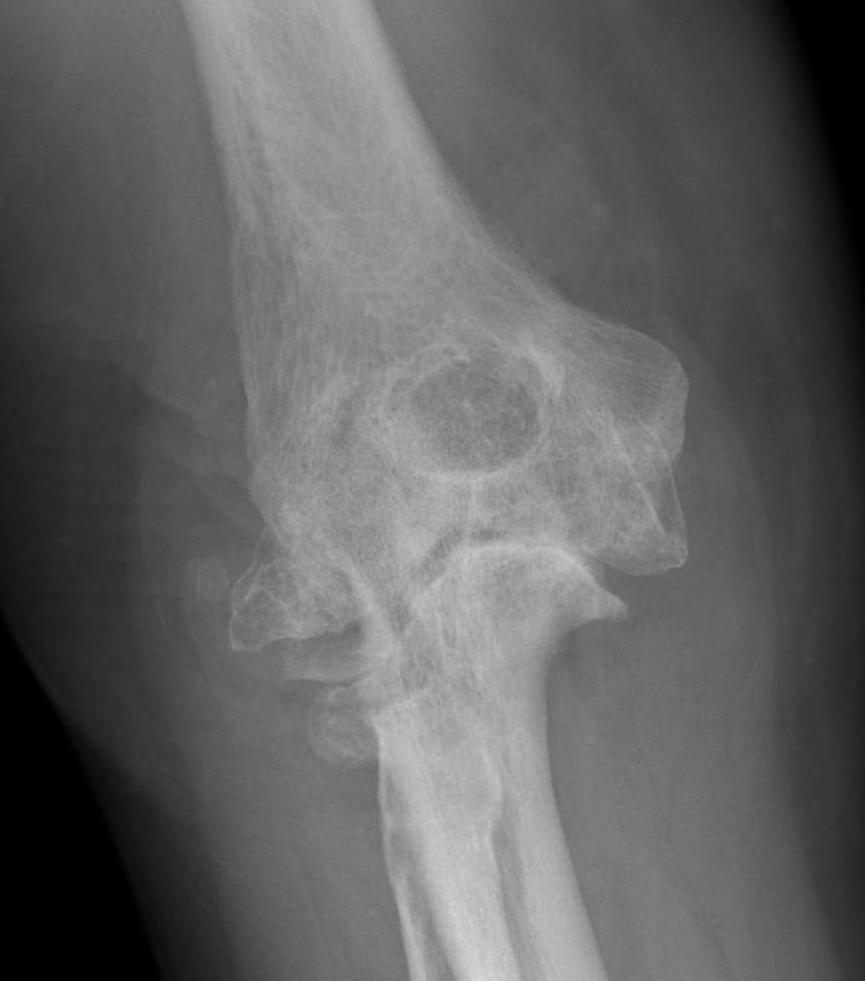

X-ray

Early stage

- preserved radiocapitellar and ulnohumeral joints

- osteophytes of the olecranon and coronoid

Lateral xray demonstrating olecranon and coranoid osteophytes